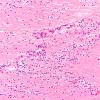

HIV Encephalitis (2)